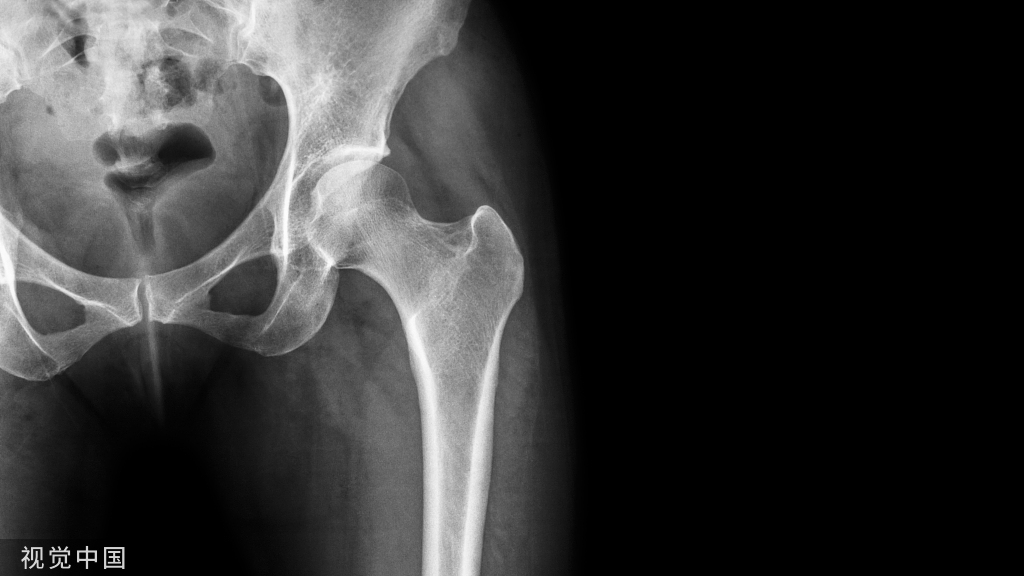

骨性结构

踝关节:全身持重关节

组成:由胫骨下端和内、外踝构成的踝穴及距骨体共同组成。

包括:骨、韧带、肌腱、软骨、滑膜等结构